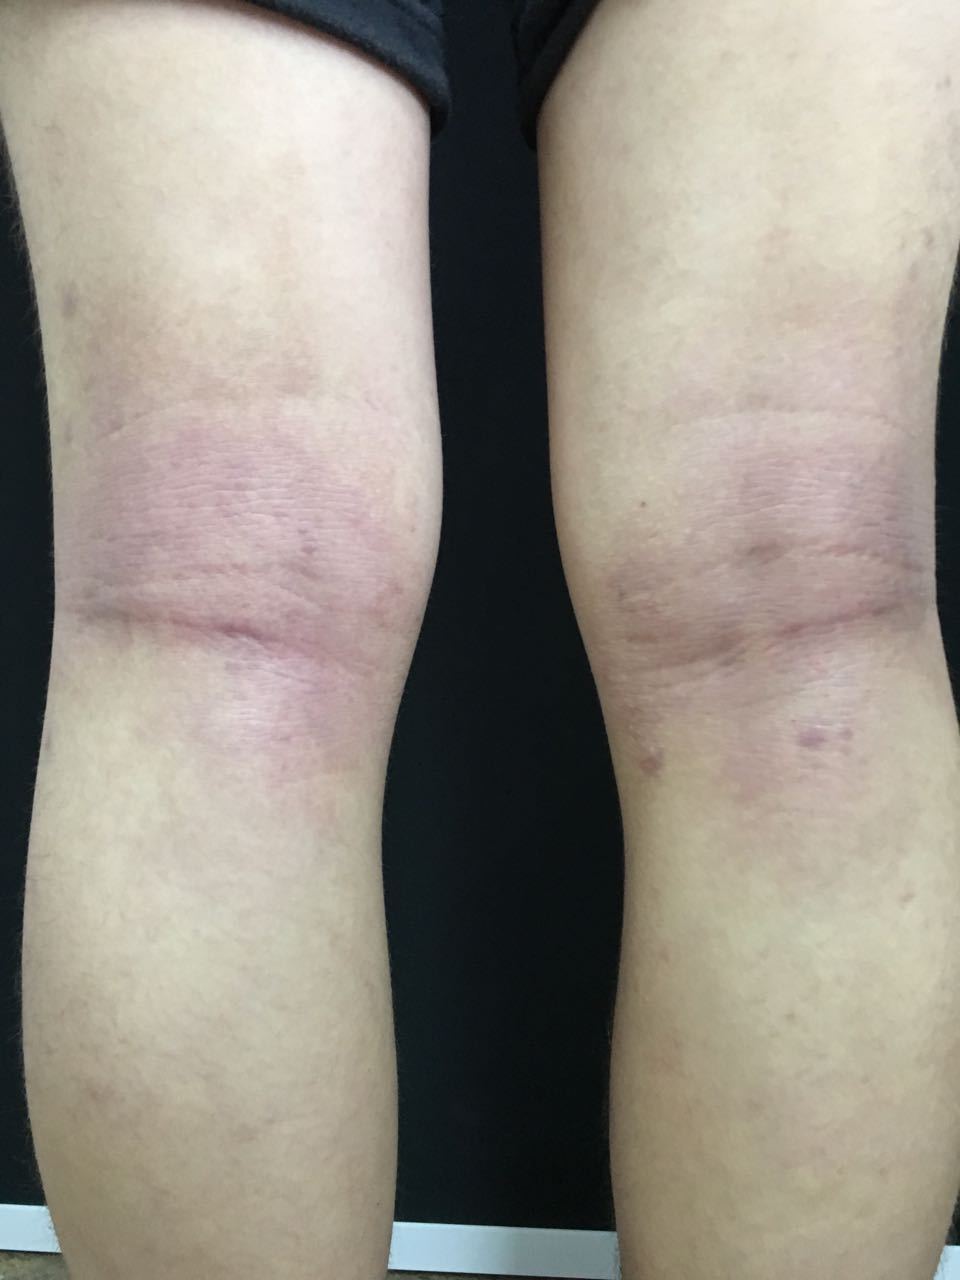

在临床表现上,特应性皮炎分为三个期,2岁以内的称为婴儿期,这一时期的发病很容易被误认为湿疹;儿童期是2-12岁,多出现在四肢屈侧、有褶皱的地方如颈窝、肘窝、腘窝等处,中医称之为“四弯风”,发作部位通常出现红斑脱屑、皮肤粗糙增厚、色素沉着;12岁以上则属于青年成人期,通常皮损范围会更为广泛。据悉,60%的特应性皮炎都发生在儿童期,非常考验家长的耐心。

特应性皮炎发病经常在颈窝、肘窝、腿窝等初。